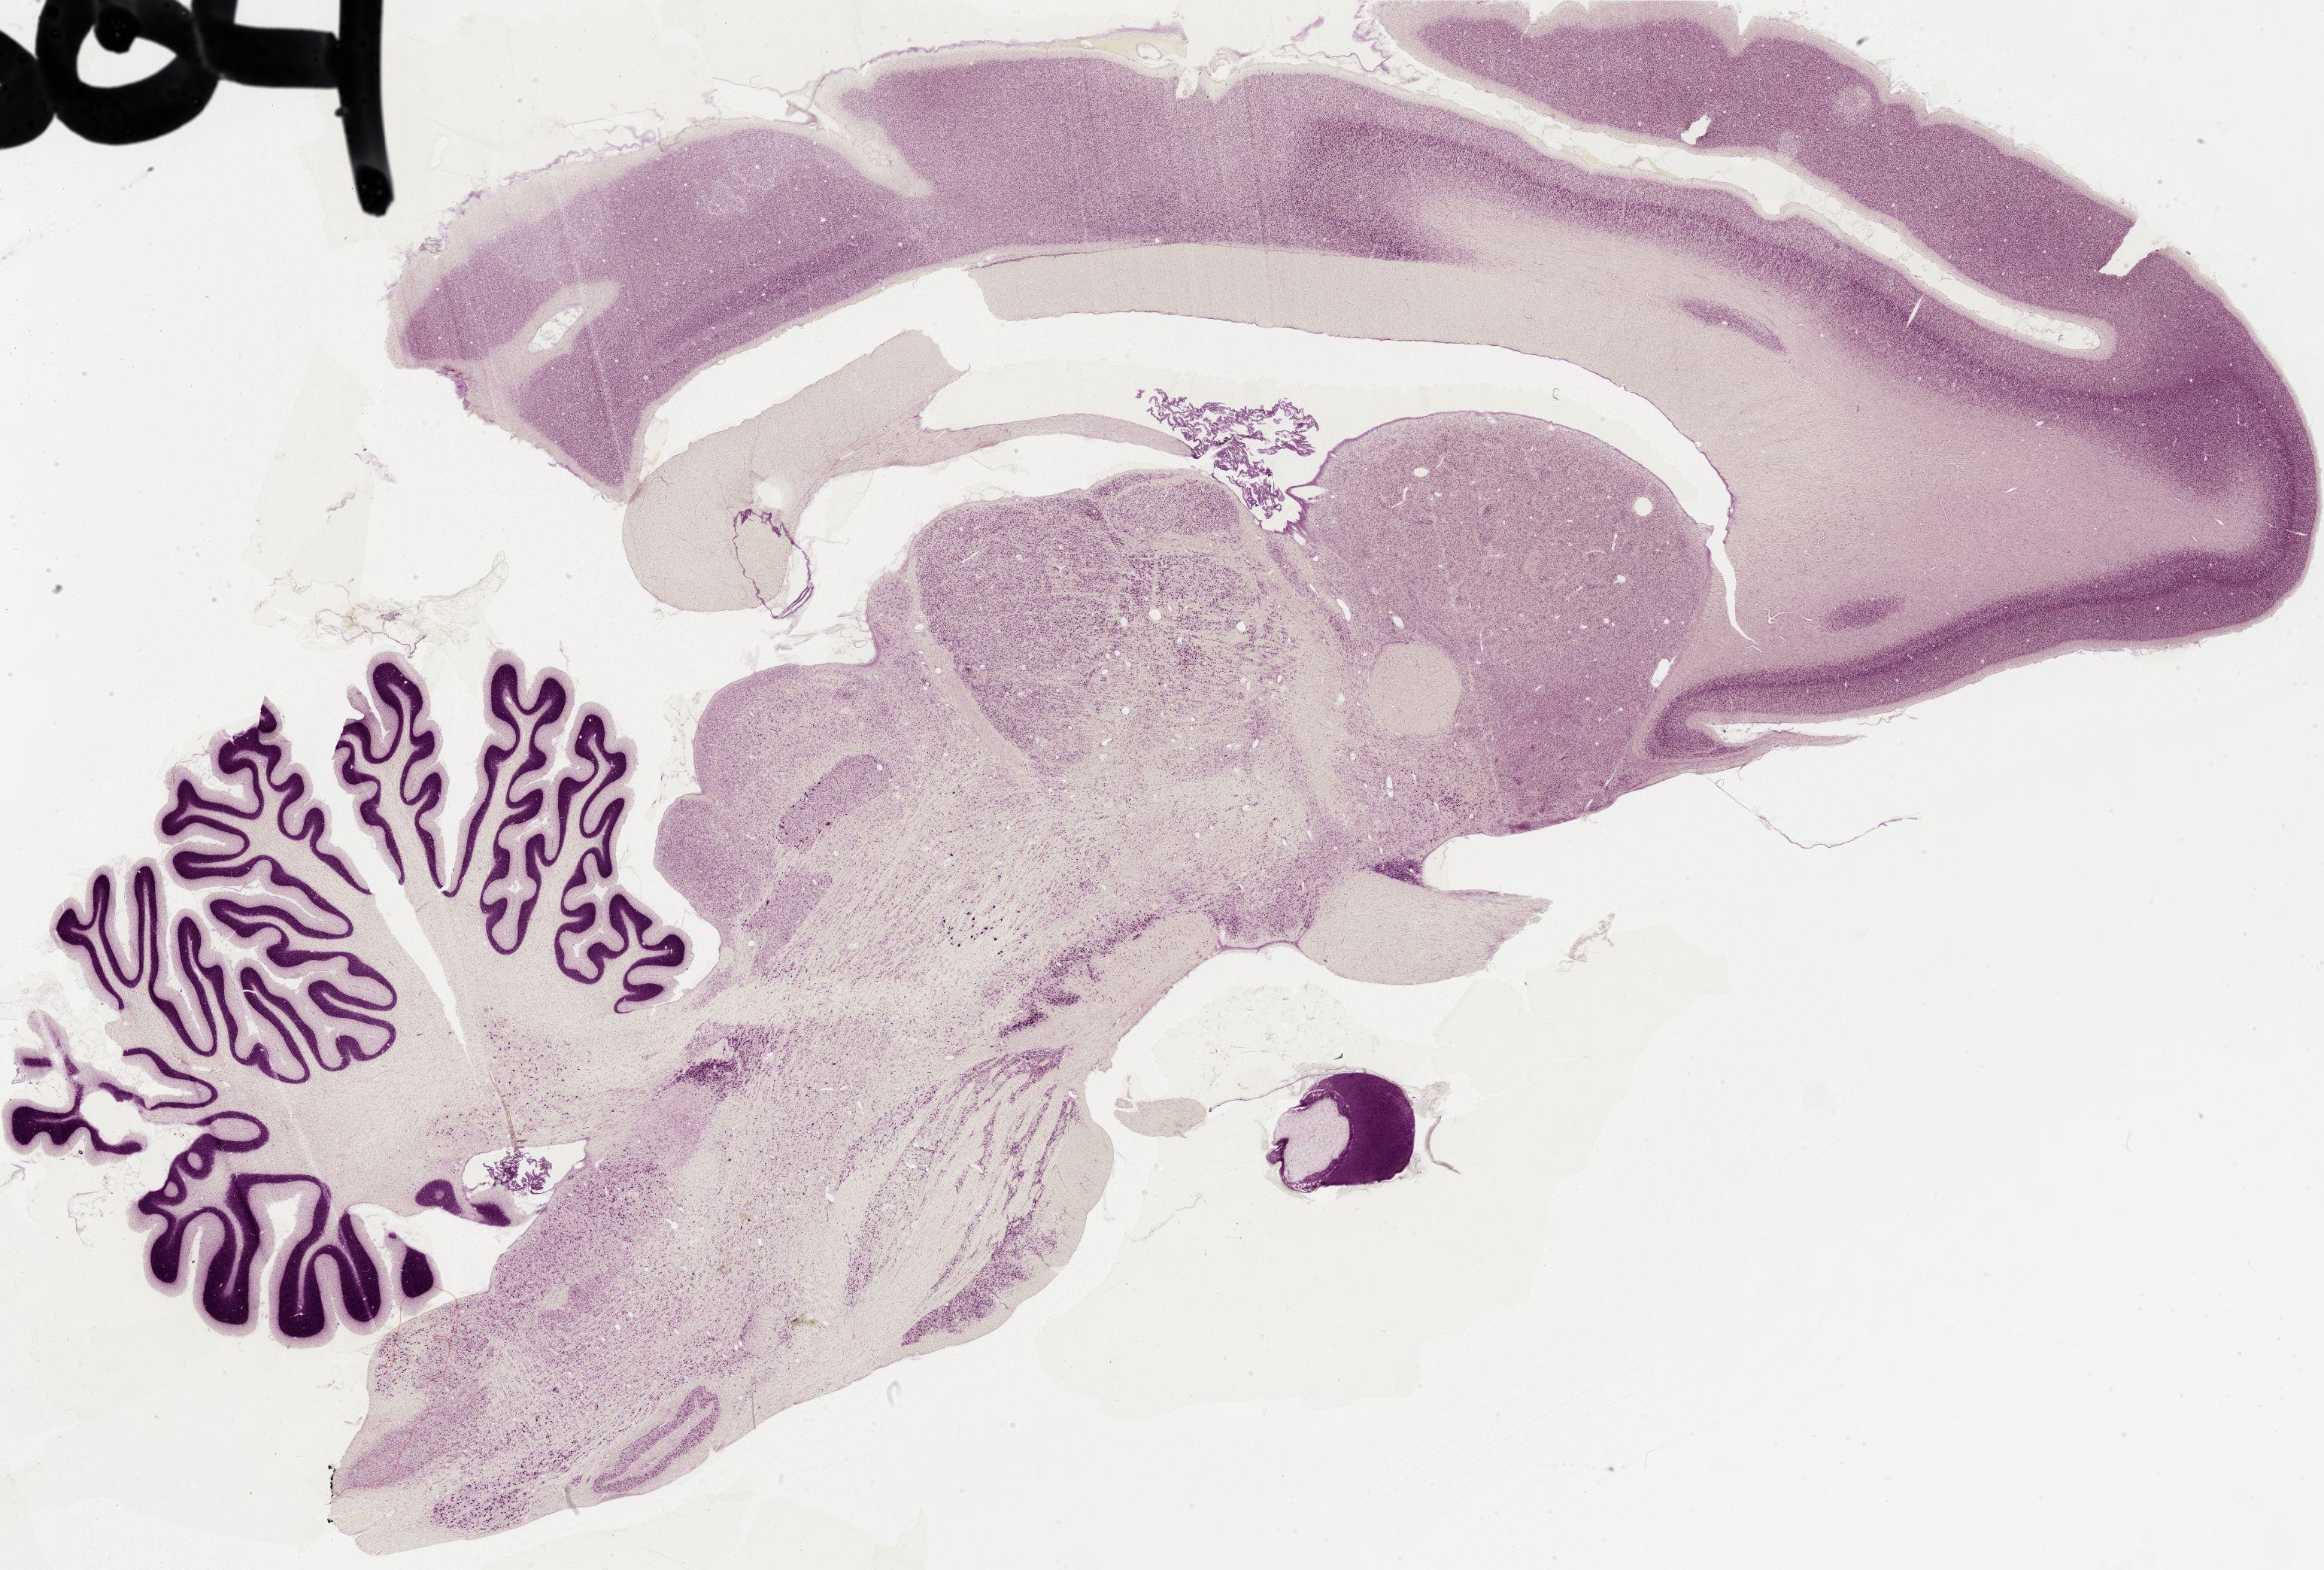

Datasets -> Macaca Mulatta -> Nissl, sagittal, histo, Whole-Brain, adult

[ Metadata ]   ·   Source: Edward G. Jones

0504 - labeled